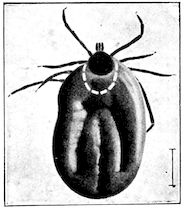

| Louping-ill | 429 | |||

| Suggested measures for prevention | 435 | |||